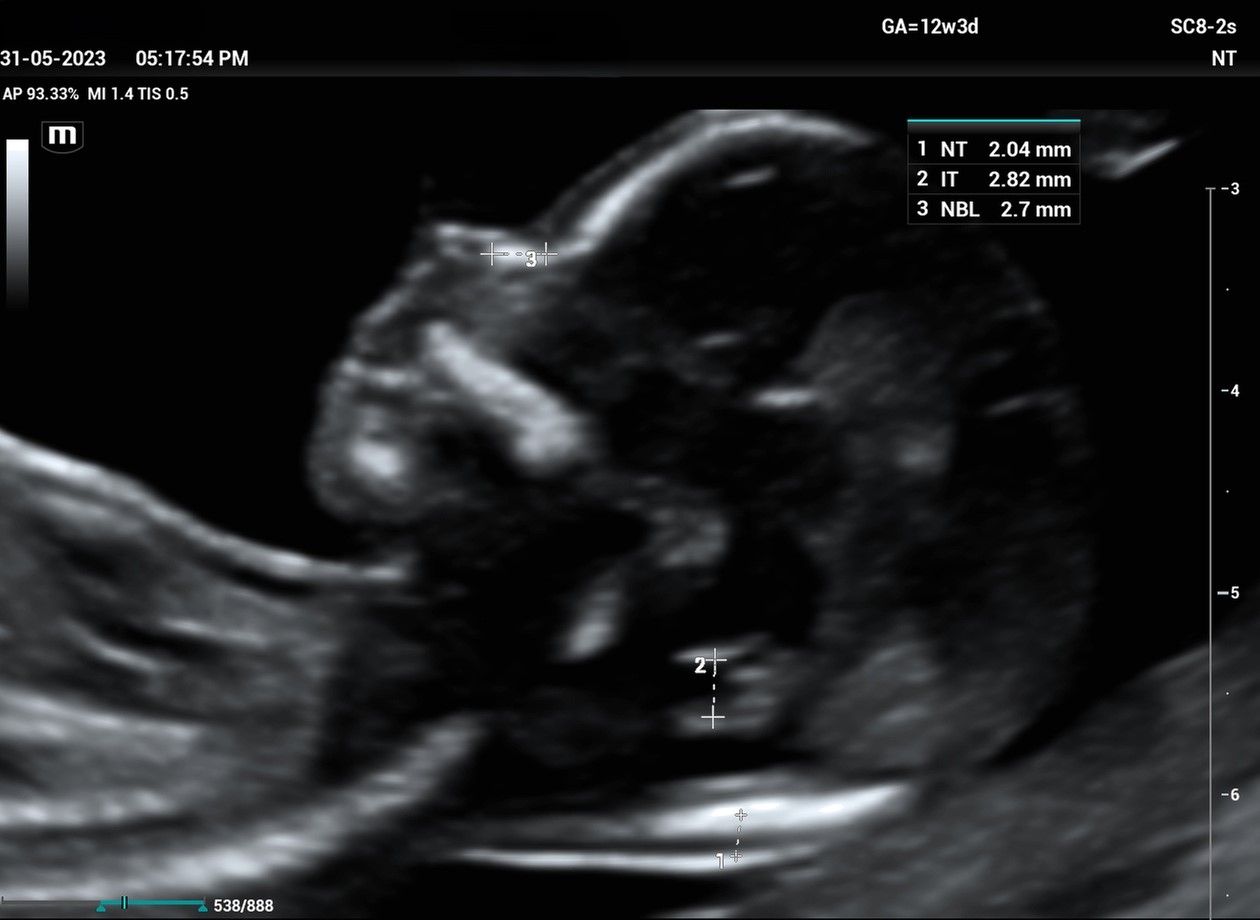

• Combined First trimester screening/ NT scan(+/

• Preterm preeclampsia screening)